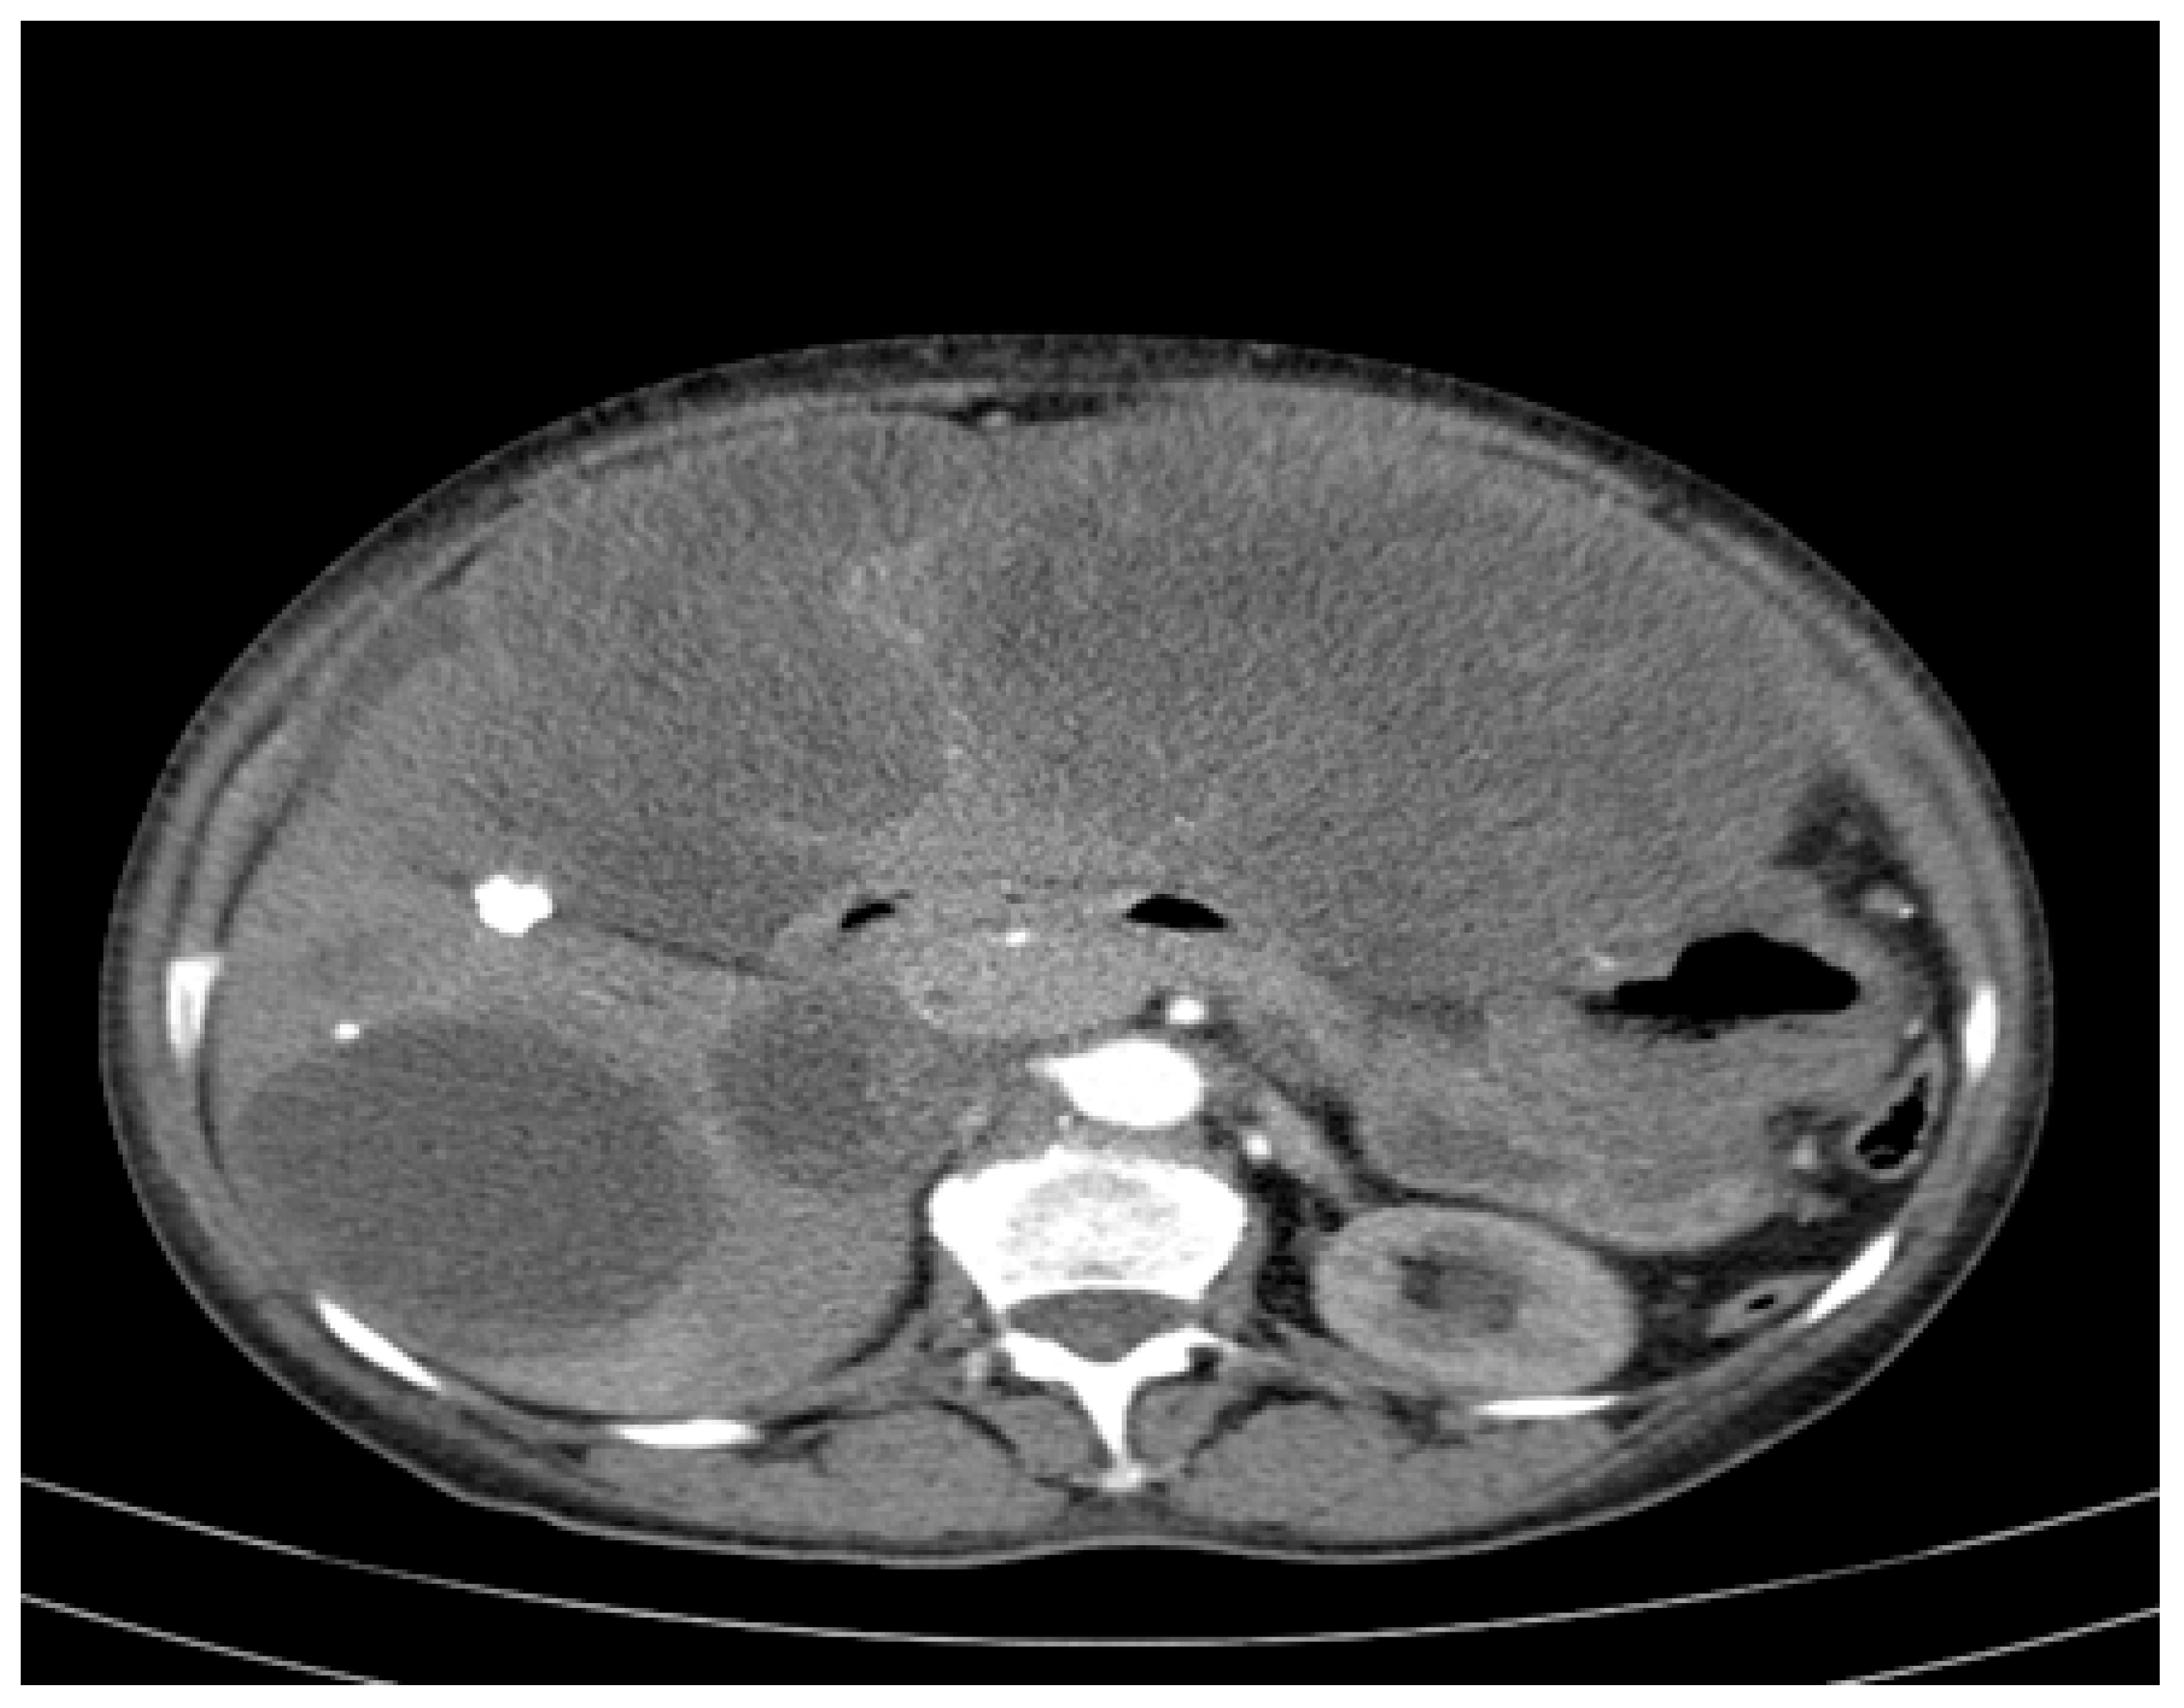

An abdominopelvic CT revealed liver enlargement due to the presence of numerous cystic lesions ranging in size from 1 cm to 18 cm, most of them located in the right hepatic lobe (Figure 1). Two of the largest cystic formations were located at the inferior liver margin, one in segment IVb and the other in segment III of the left hepatic lobe, occupying almost the entire abdominal cavity. The inferior pole of the cystic formation arising from the left hepatic lobe extended into the pelvic cavity (14 × 18 × 18.5 mm AP/Transverse/CC), displacing the transverse colon posteriorly and shifting the jejuno-ileal loops toward the right iliac fossa. The cysts had well-defined contours, but their inner walls varied in thickness and exhibited heterogeneous contrast enhancement. Three hepatic parenchymal calcifications were present in the right hepatic lobe (segments V and VI), with the largest measuring 14 mm and the smallest 2–3 mm; two of them were adjacent to the cystic wall. A thin layer of perihepatic/hepatodiaphragmatic fluid was also noted, with an uneven thickness ranging from 1 to 2.3 cm.

Figure 1.

CT appearance at the time of diagnosis: hepatic tumour formations with a cystic morphology, showing walls of variable thickness and heterogeneous contrast enhancement.